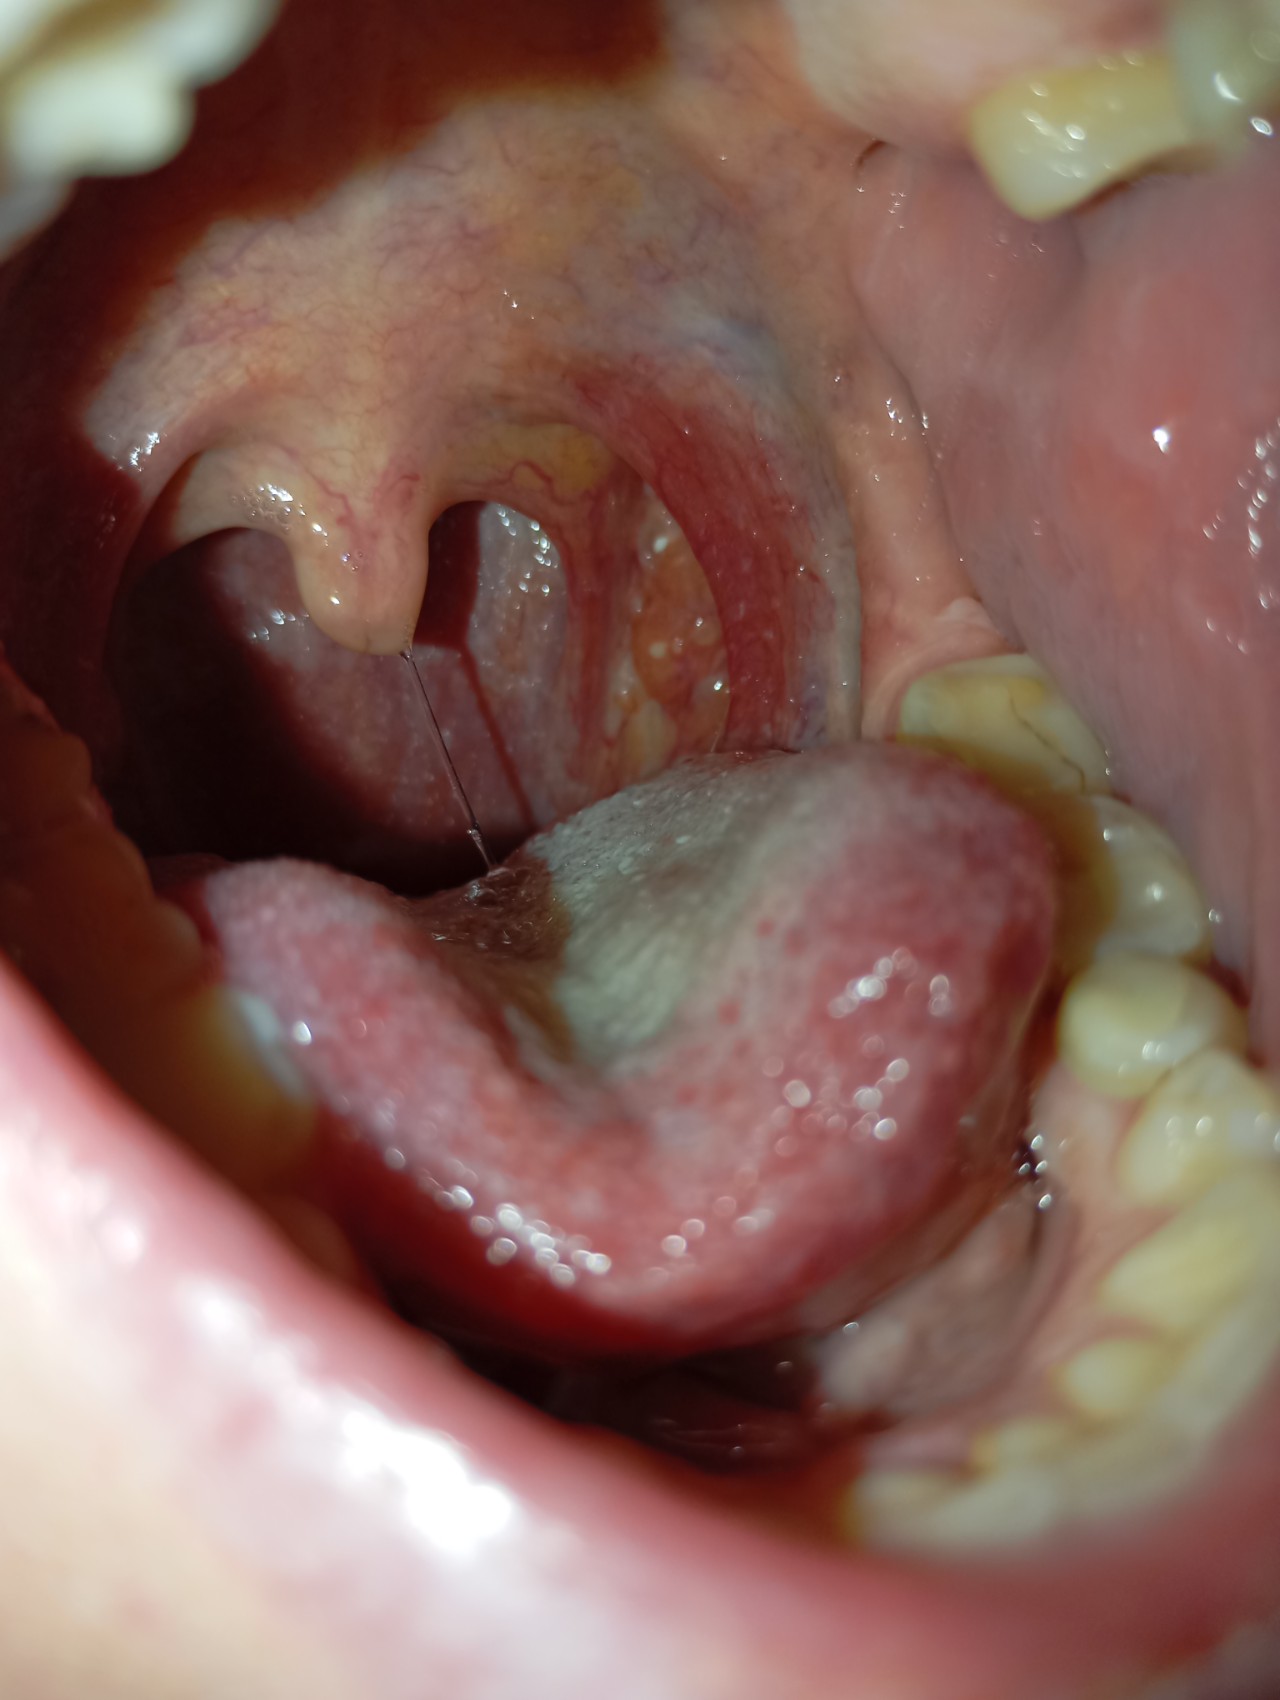

Здравствуйте, недавно стало першить в горле совсем немного, чуть покашливала. Посмотрела в зеркало и обнаружила около миндалины, чуть сбоку, какое -то образование, как маленький нарост, не отличающийся по цвету от остальной ткани. Подскпжира, пожалуйста, это нормально? Очень переживаю, спасибо!